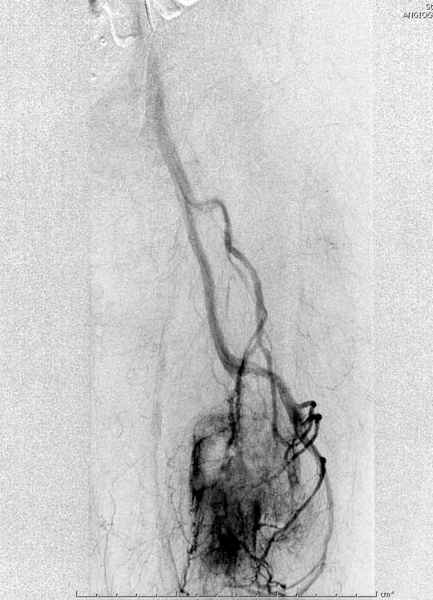

Для предупреждения кровотечения во время рассверливания, за день до операции провели эмболизацию сосудов питающий метастаз. http://radiology.rsnajnls.org/cgi/reprint/150/3/673.pdf (7-11, 12-15-16)